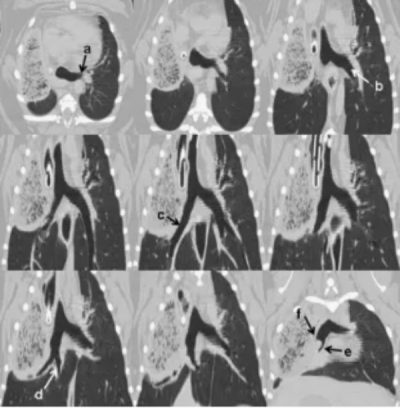

回顾性分析影像方案的图像细节、运动伪影和重建图像质量。所有图像由一名委员会认证的放射科医师(G.S.)进行回顾性审查,评估扭转肺叶内的变化、剩余肺内的变化以及胸腔内的其他变化。特别使用不同平面的重建图像评估支气管解剖结构。此外,还进行了桨轮重建(paddle wheel reconstructions),围绕支气管分叉点旋转重建平面,以评估支气管树的走行(图1)。

图1. 一只患有右前肺叶扭转的2岁巴哥犬桨轮重建计算机断层扫描(CT)影像。从横断面(左上图)开始,沿支气管分叉处(左上至右下方向)进行多平面重组。所有支气管清晰可辨:a. 左前叶支气管;b. 左后叶支气管;c. 右后叶支气管;d. 副叶支气管;e. 塌陷的右中叶支气管;f. 通向扭转右前肺叶的极短盲端支气管。

尤其对于评估支气管的位置、走向和管径而言,多平面图像重组技术具有重要价值。桨轮重建法以支气管分叉处为旋转中心进行重建平面旋转,该技术专为优化大气道及大血管自然走行的评估而开发。由于旋转中心位于支气管分叉点,中央大气道结构在连续图像中清晰呈现,可被视觉追踪至肺外周区域(图1)。主观评估表明,当原始序列采用薄层厚、连续轴位扫描层间距或低螺旋螺距采集时,重组图像的诊断效用最为显著。